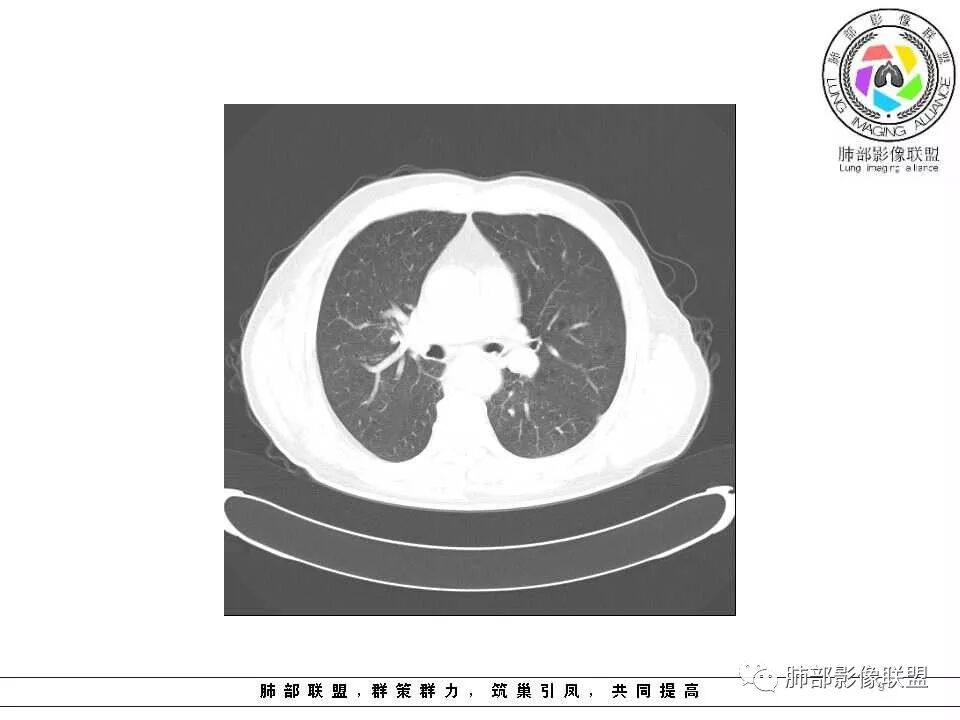

老年男性,两肺可见小叶中央型肺气肿,提示应该有抽烟史。2016年片,右肺门支气管稍模糊,考虑慢性感染,纵膈淋巴结稍大。但2017年左肺上叶新发占位,堵塞支气管,引起局部肺不张伴感染,且纵膈淋巴结较2016年变大,患者同时伴有咯血,考虑恶性。鳞癌?类癌?小细胞?

肺气肿背景,2016年左肺上叶上舌段见微结节,2017年5月左肺结节增大,密度均匀,边缘光滑锐利,与邻近血管关系密切,血管贴壁走行,外侧见尖状突起,下舌段片状影,沿着支气管走行,内有粘液栓,考虑鳞癌,鉴别小细胞肺癌。

肺气肿背景,2016年左肺上叶上舌段见微结节,一年后左肺结节增大,密度均匀,边缘光滑、膨隆,似见小分叶,下舌段片状影,沿着支气管走行,内,老年患者,咯血1月。考虑恶性病变并阻塞性肺炎,鳞癌?注意鉴别结核。

老年男性,咯血1月,肺气肿背景,16年左肺上叶舌段结节,左肺门疑似淋巴结肿大,呈结节感。17年左肺上叶舌段见沿支气管走行分布结节 远端阻塞性肺炎,左肺门淋巴结肿大明显,首先考虑恶性病变,鳞癌?类癌?

前次片2016年4月20相应位置就有小点状病灶,2017-5-15呈结节影改变,边界膨隆,远端阻塞炎性改变,考虑肺癌,鉴别炎性结节!

老年男性,肺气肿背景,左肺上叶舌段一年前小结节后长大,实性,与邻近气管关系密切,远端有少许小片状炎症类小结节状,左肺门淋巴结肿大,首先考虑恶性,鳞癌可能性大,代排小细胞癌。病灶下方斑片状影,考虑炎症。

老年男性,肺气肿背景,对比前片,左肺上叶舌段结节较前进展,周围有斑片状条状密度增高影,左肺门淋巴结肿大,有咯血史抗炎后效果不佳,目测增强强化不好判断,考虑肺癌并阻塞性肺炎可能,鉴别炎症性肺癌,真菌类肺炎,肺脓肿,肺结核,建议完善肿瘤标志物,结核相关检查,病原体检查。

后头看前片似乎当时腔内壁稍增厚一点

那就是说这是新发的